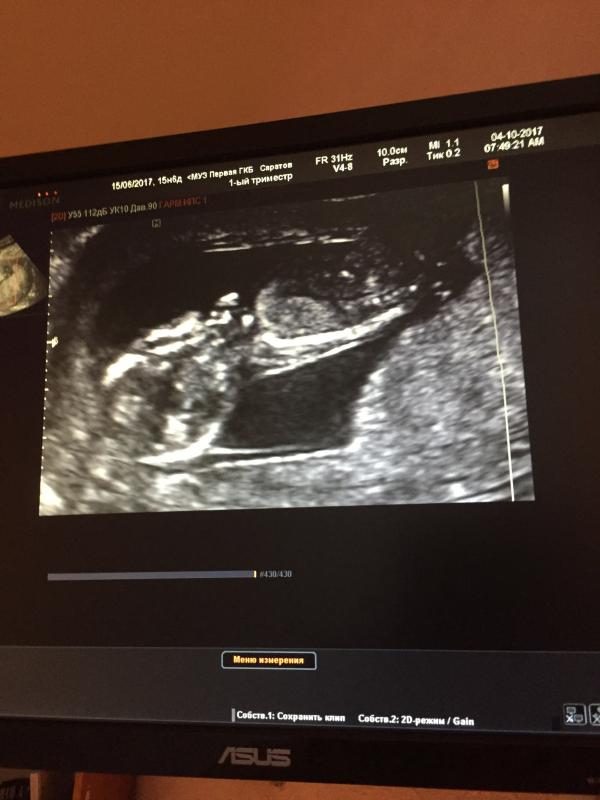

Сегодня была на 1 скрининге, так волнительно 😍как будто первая беременность когда ничего не знаешь не опытна , вообщем все нормально тьфу тьфу тьфу , шов хороший , эмбрион прикреплён по задней стенке . Врач смеётся что рожай не хочу . Так как я прям расплакалась как только на экране стало видно малыша . Пуповина была между ног и не разглядели кто там сидит 😩но самое главное для меня это пусть будет здоровой 😘моей любви хватит на всех 😁ну и первое фото моего малыша, хотя там плохо видно но это са...